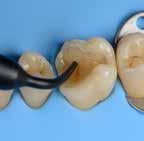

Restoring incisal wear and closing diastema with G-aenial A’CHORD. Courtesy of: Dr Aleksandra Slacan, Poland

Reshaping of teeth and diastema closure with G-aenial A’CHORD. Courtesy of: Dr Andres Silva, Spain